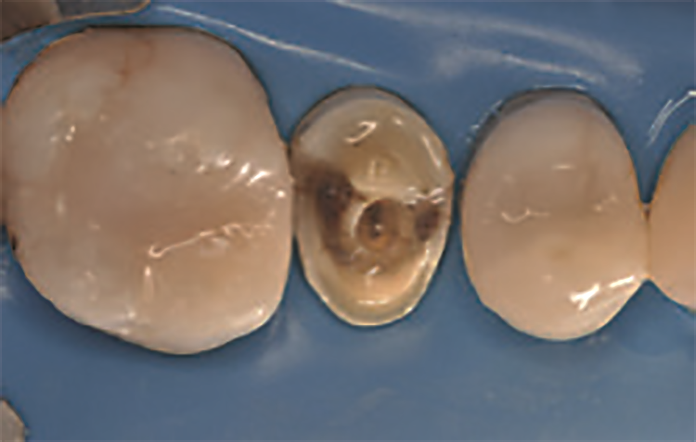

47‑letnia pacjentka zgłosiła się z powodu objawów zapalenia miazgi zęba 15. W badaniu wewnątrzustnym stwierdzono obecność starego wypełnienia amalgamatowego oraz złamanie guzka policzkowego zęba 15 (ryc. 1 i 2). W związku z tym na pierwszej wizycie przeprowadzono leczenie endodontyczne zęba 15 w znieczuleniu miejscowym (ryc. 3).